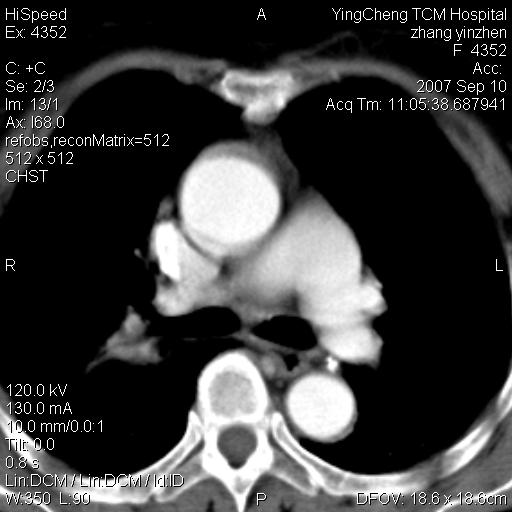

以下是引用卜一在2007-9-18 14:41:00的发言:[br]右肺肿块:毛刺+胸膜凹陷征+供血血管+浅分叶+强化。支持:周围性肺癌 !另:左侧甲状腺腺瘤!

以下是引用夏季在2007-9-18 11:00:00的发言:[br]1。右肺肿块,周围有短毛刺,肺门侧有血管与其相连,胸壁侧有胸膜凹陷征,考虑周围性肺癌 2。左侧甲状腺软组织肿块,内有高密度钙化灶,考虑左侧甲状腺腺瘤。